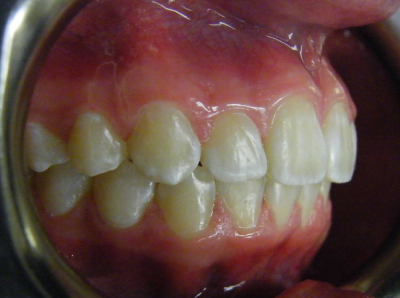

The first two sets of photos below are the before and after photos of a patient who had expansion of the upper jaw followed by upper and lower fixed braces. The third set of photos shows a patient with an expansion plate bonded to the upper teeth and lower fixed braces.